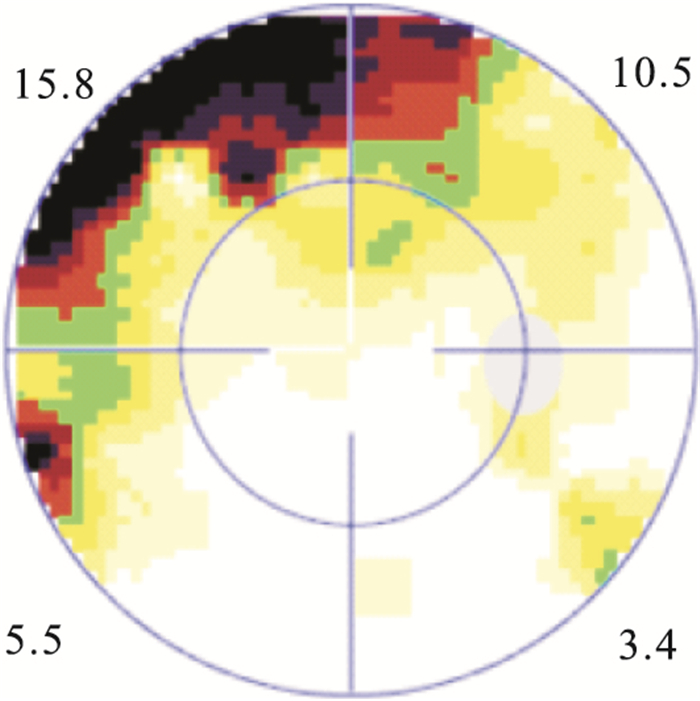

手術后1、2周,1、3、6、12個月,平均MD值分別為(11.38±2.53)、(10.14±2.19)、(9.17±2.13)、(6.63±1.70)、(5.71±1.89)、(5.14±1.69)dB。各觀察時間點平均MD值比較,差異有統計學意義(F=63.528,P=0.00)。手術后6、12個月平均MD值比較,差異無統計學意義(t=1.442,P=0.157)。手術后12個月,MD值恢復正常12只眼;偏高30只眼。MD值偏高的30只眼與對側眼MD值比較,差異無統計學意義(t=-1.936,P=0.06)。視網膜微結構恢復正常15只眼中,MD值偏高6只眼。相關性分析結果顯示,視網膜微結構正常者平均MD值與手術前視網膜脫離時間呈正相關,差異有統計學意義(r=0.84, P=0.00),并且視野缺損多位于裂孔區(圖 4)。

患眼手術后6個月視野檢查圖。鼻上方裂孔區域仍有視野缺損

患眼手術后6個月視野檢查圖。鼻上方裂孔區域仍有視野缺損

手術后1、2周,1、3、6、12個月,平均MD值分別為(11.38±2.53)、(10.14±2.19)、(9.17±2.13)、(6.63±1.70)、(5.71±1.89)、(5.14±1.69)dB。各觀察時間點平均MD值比較,差異有統計學意義(F=63.528,P=0.00)。手術后6、12個月平均MD值比較,差異無統計學意義(t=1.442,P=0.157)。手術后12個月,MD值恢復正常12只眼;偏高30只眼。MD值偏高的30只眼與對側眼MD值比較,差異無統計學意義(t=-1.936,P=0.06)。視網膜微結構恢復正常15只眼中,MD值偏高6只眼。相關性分析結果顯示,視網膜微結構正常者平均MD值與手術前視網膜脫離時間呈正相關,差異有統計學意義(r=0.84, P=0.00),并且視野缺損多位于裂孔區(圖 4)。

患眼手術后6個月視野檢查圖。鼻上方裂孔區域仍有視野缺損

患眼手術后6個月視野檢查圖。鼻上方裂孔區域仍有視野缺損

視野相對于中心視銳度而言,它主要反映了周邊視野。MD是反應全視網膜光敏感度是否下降及下降的程度,受變異的影響較小,有利于對患者的隨訪。本研究通過對手術前后MD觀察發現,累及黃斑的視網膜脫離手術后MD逐漸減小;至手術后6個月視網膜缺損處于穩定狀態,與手術后12個月MD值比較,差異無統計學意義。本研究結果顯示,即使OCT檢查視網膜微結構正常的15只眼中,仍有6只眼視野未恢復正常,且未恢復的缺損區多位于視網膜裂孔處。我們認為此種情況與患者視網膜脫離時間較長有關。本組患者視網膜脫離時間平均為(21.12±3.71) d,而有研究發現,視網膜脫離12 h,細胞即出現凋亡,且以前3 d為著。隨著視網膜脫離時間延長,視網膜下液積存,視網膜缺乏脈絡膜層的血液供應,光感受器和RPE層間的物質轉運障礙,即使手術后視網膜解剖復位,視網膜光感受器細胞層功能受損難以恢復,影響視野預后。LV是視野形狀與正常視野形狀的相差程度,主要反映局部視野的缺損[13]。本研究中,患眼LV手術后逐漸減小,前6個月變化較快,至手術后12個月尚有19只眼未恢復正常,可能與MD變化有關。